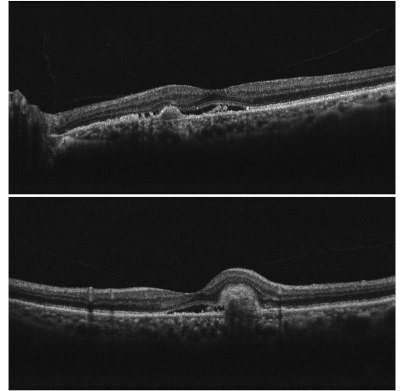

73歳の男性。左眼の視力低下と物が歪んで見えることとを主訴に来院した。症状は6か月前から始まり最近になって増悪したため受診した。矯正視力は右眼1.2、左眼0.3。左眼の眼底写真と光干渉断層像とを別に示す。右眼眼底に異常を認めない。